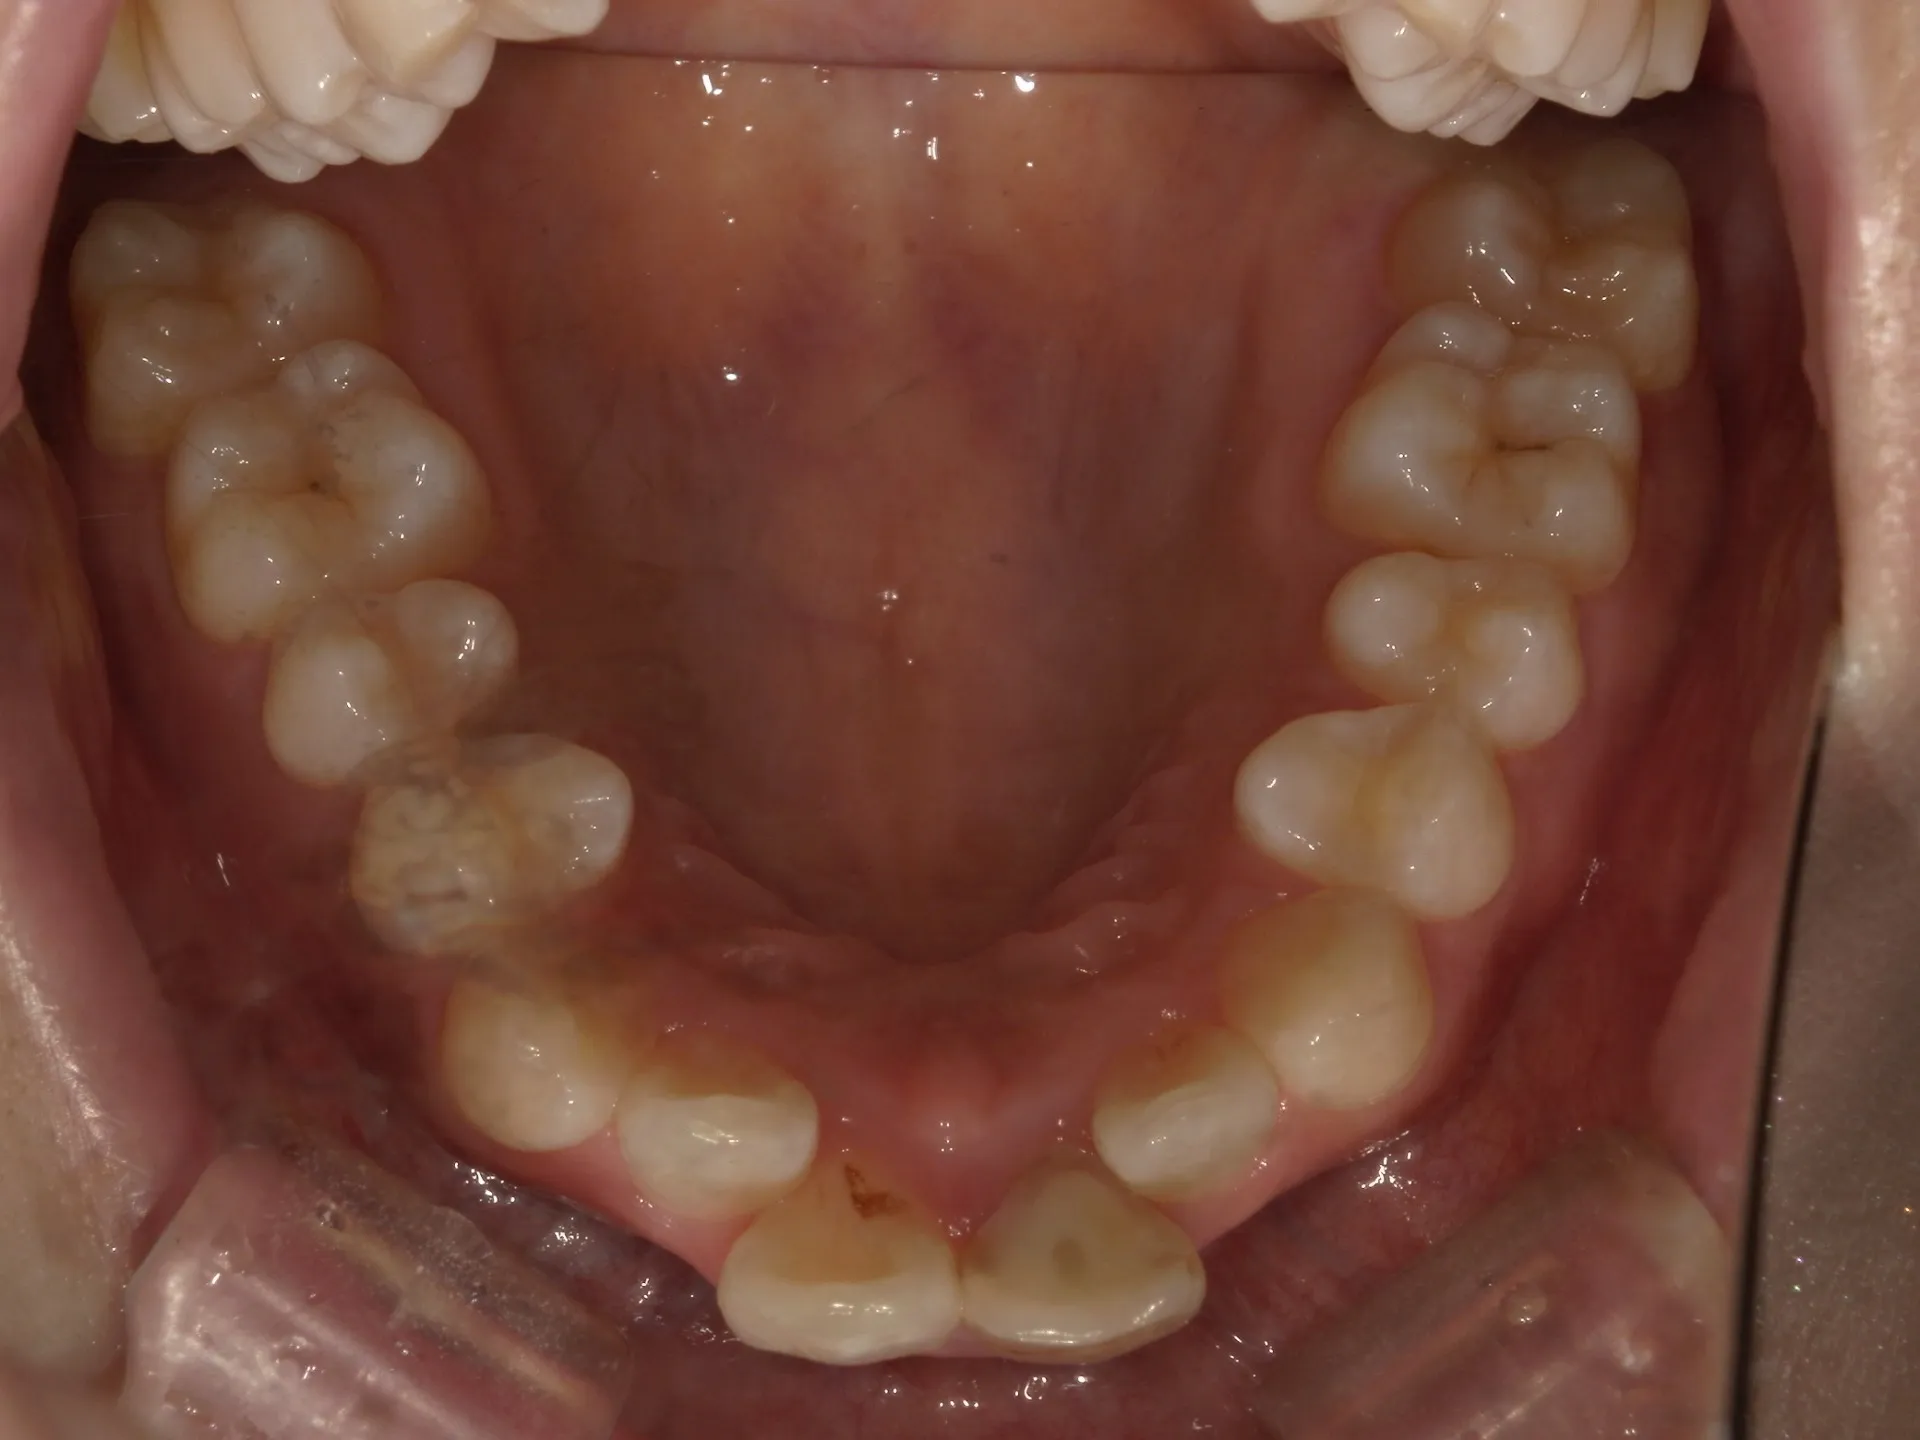

大きく飛び出してしまった前歯の矯正と変色の治療を希望された症例をご紹介いたします。